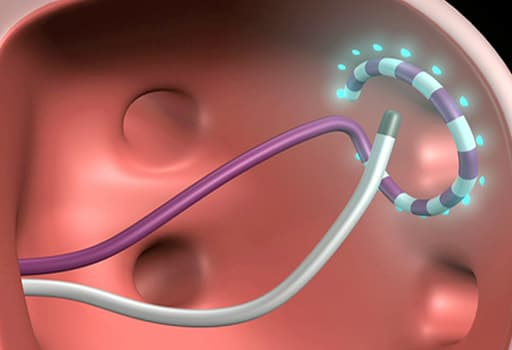

先天性心脏病的经导管封堵;

-

传统的经导管瓣膜治疗术:

经皮二尖瓣球囊扩张(percutaneous balloon mitral valvuloplasty,PBMV)

经皮肺动脉瓣球囊扩张(percutaneous balloon pulmonary valvuloplasty,PBPV)

经皮主动脉瓣球囊扩张(percutaneous balloon aortic valvuloplasty,PBAV),

经导管瓣周漏封堵(Paravalvular Leak closure)等。

经导管左心耳封堵技术(Transcatheter left atrial appendage occlusion);

射频消融(Catheter Ablation),如

室上性心动过速导管消融术(Catheter Ablation for Supraventricular Tachycardia)

房颤导管消融术(Catheter Ablation for Atrial Fibrillation)

室性心动过速导管消融术(Catheter Ablation for Ventricular Tachycardia)

和手术混合房颤消融(Surgical Hybrid AF Ablation)等